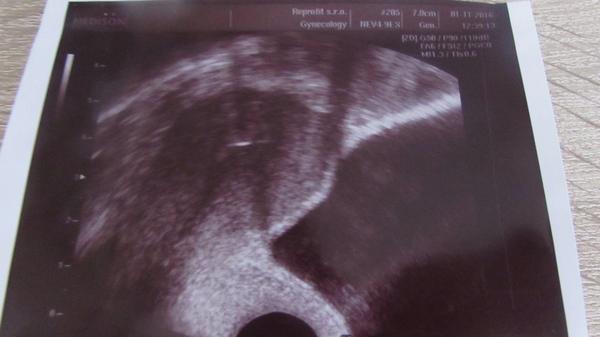

Reprofit Brno. Máte zkušenosti?

Ahoj holky, chceme z Jihlavy přejít a dostali jsme doporučení, aby jsme zkusili Reprofit. Mohu poprosit o info jak jste spokojené a popř. jakého dokotra zvolit? Děkuji. 🙂

Ahoj holky, vcera jsem byli na porade o budoucim mimi. Mame zamrazene 2 pajetky, po 2 embryjkach.... Pridelili nam mudr Kneslovou... Mate nektera zkusenost? Prvni ditko mame od Stelcla 🙂 . Docela me zarazilo, ze se musi rozmrazit obe emryjka a jedno nasledne zamrazit... Dve mi nedaji. Jsem po CS a dvojcata se vyrazne nedoporucuji...